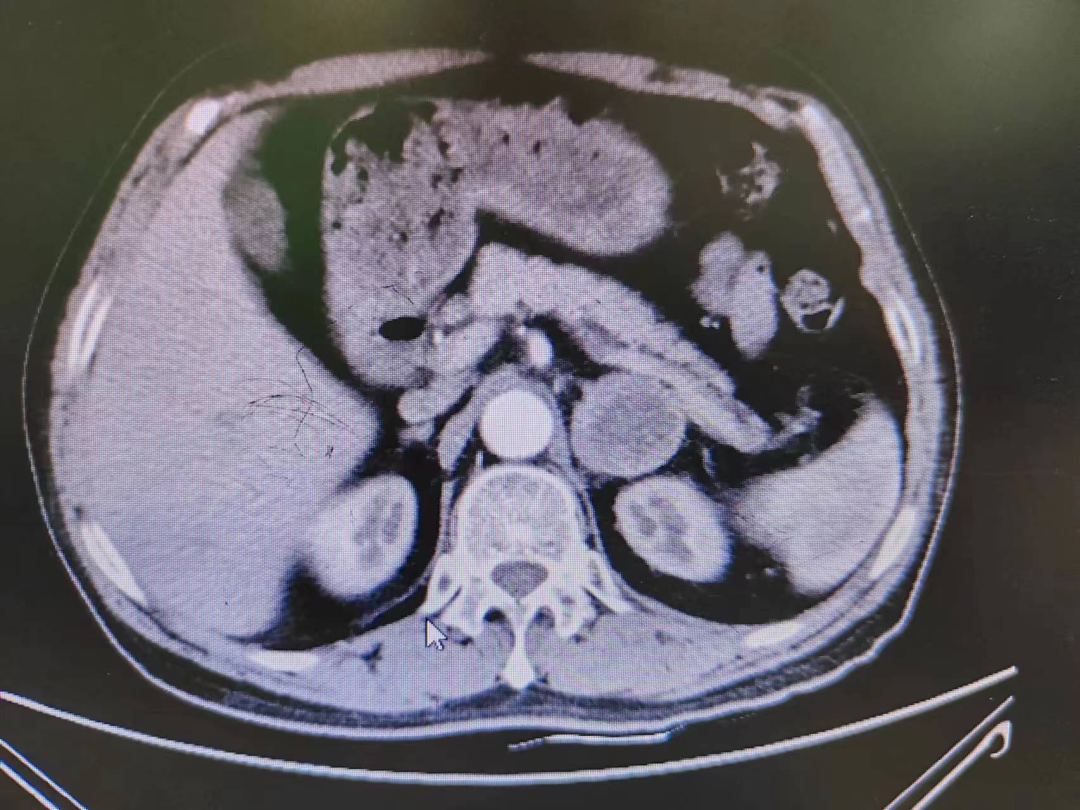

嗜铬细胞瘤及副神经节瘤是一类内渗透系统的少见病,,, ,,,嗜铬细胞瘤是起源于肾上腺髓质,,, ,,,副神经节瘤是起源于肾上腺外的交感神经链并具有激素渗透功效的神经内渗透肿瘤,,, ,,,主要合成、渗透和释放大宗儿茶酚胺,,, ,,,引起患者血压升高和代谢性改变等一系列临床症候群,,, ,,,并造故意、脑、肾、血管等严重并发症甚至成为患者殒命的主要缘故原由。。。。。。。

患者熊XX,,, ,,,67岁,,, ,,,因发明头晕、头痛曾多次于外院就诊,,, ,,,到新桥医院就诊完善肾上腺CT思量嗜铬细胞瘤,,, ,,,既往有高血压病史3年,,, ,,,血压更高达230/120mmHg。。。。。。。我院高新区院区开诊后,,, ,,,患者慕名而来。。。。。。。术前起劲完善血尿儿茶酚胺代谢产品(MNS)均显着升高,,, ,,,患者于我院高新区院区及江南院区泌尿外科起劲控制血压、心率、血糖,,, ,,,术前充分扩容。。。。。。。

因肿瘤位置位于肾蒂周围,,, ,,,术中触碰肿瘤导致血压显着升高,,, ,,,血压波动较大,,, ,,,肿瘤外貌血供富厚,,, ,,,不但需要手术医生富厚的临床履历和高明的手艺水平,,, ,,,也是对医生心理素质、勇气和毅力的严肃磨练。。。。。。。

经由泌尿外科医师全体讨论,,, ,,,在举行术前准备2-3周后,,, ,,,再次请多学科讨论评估手术危害,,, ,,,并与患者及眷属充分相同后于6月30日行腹腔镜下左侧肾上腺嗜铬细胞瘤切除术。。。。。。。手术在陈勇主任医师的指导下,,, ,,,由孙伟副主任医师主刀及王传麟医师完成,,, ,,,术中见肿瘤与肾蒂血管周围粘连细密,,, ,,,与肾动脉、肾静脉分界不清,,, ,,,稍有失慎,,, ,,,可能损伤肾蒂血管可能需要行肾切除术,,, ,,,且疏散肿瘤历程中血压波动较大。。。。。。。但在孙伟精准操作及疏散下,,, ,,,与麻醉医生和手术护士团队亲近配合,,, ,,,经由2小时的手术,,, ,,,顺遂切除嗜铬细胞瘤,,, ,,,并;;; ;;ず蒙鲈嘌芗爸芪ё橹。。。。。。。术后患者顺遂出院,,, ,,,术后血压及血糖控制优异。。。。。。。